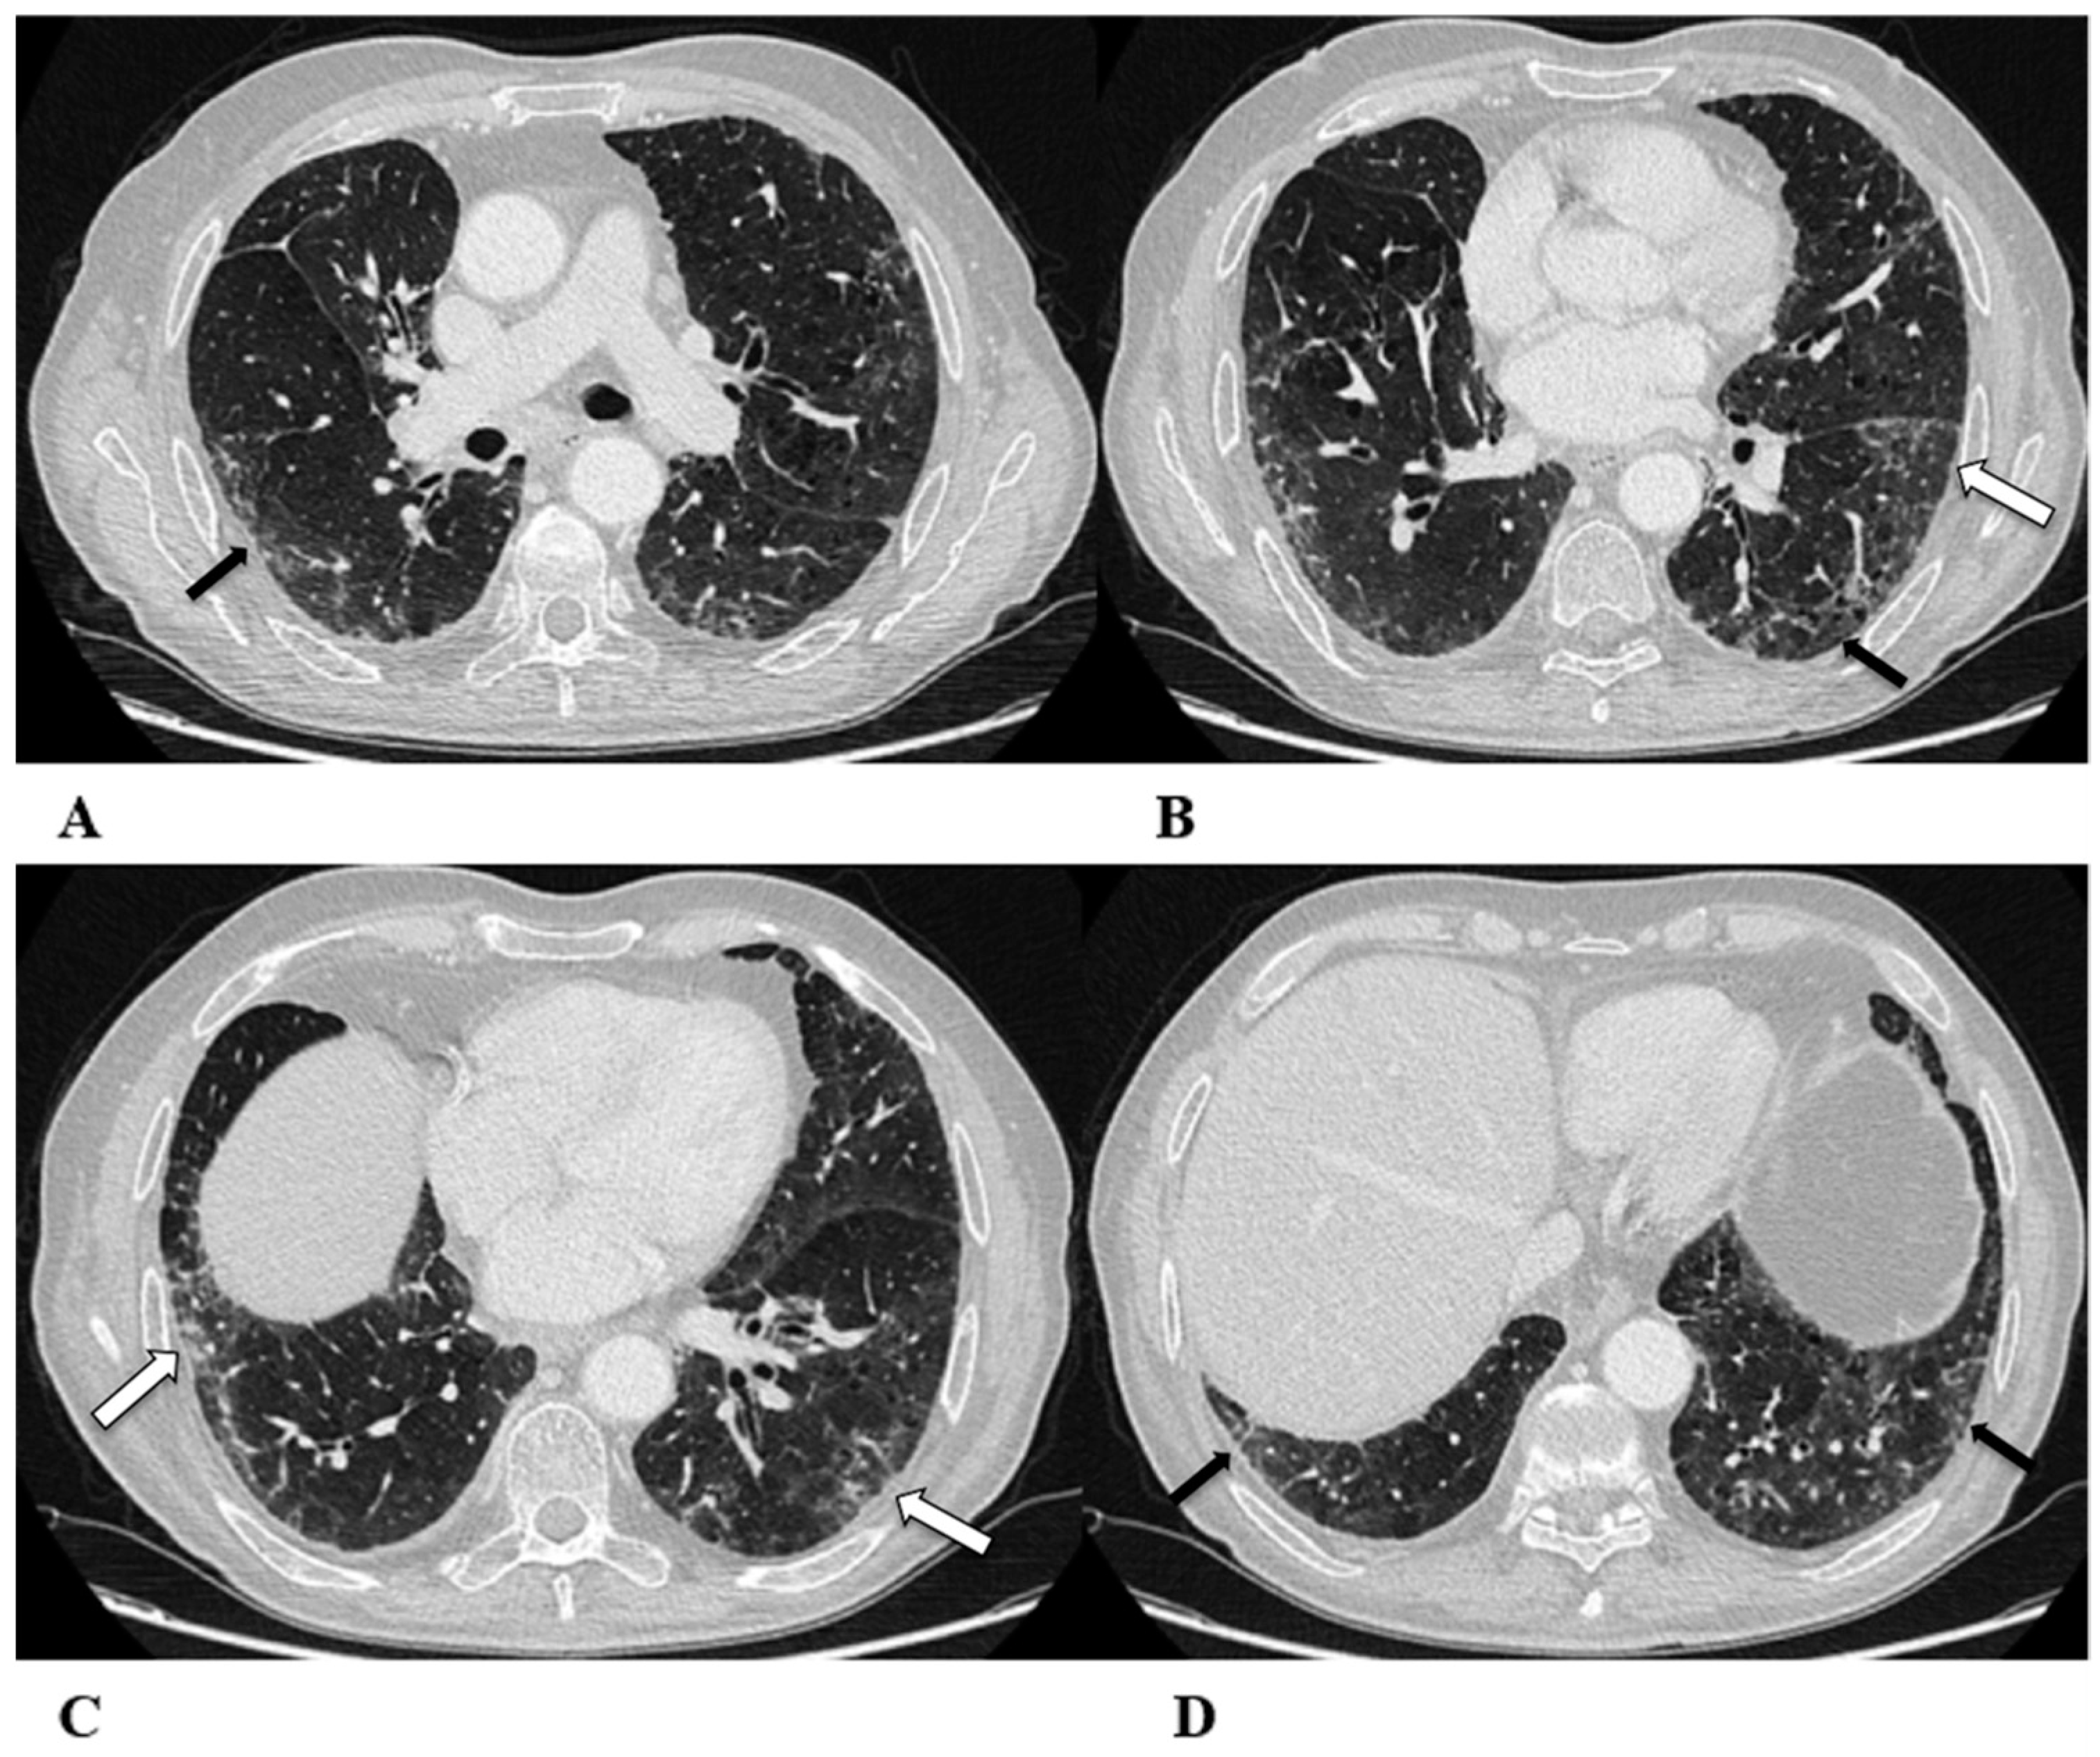

Figure 1.

Organizing pneumonia (OP). Organizing pneumonia is determined by the presence of granulation tissue buds in the alveoli, alveolar ducts and distal bronchioles. On HRCT, OP is characterized by diffuse and bilateral areas of consolidation and ground-glass opacities (GGOs), often migratory, with predominantly peripheral/subpleural and peribronchovascular distribution [9,12]. Other OP findings are the “reversed halo sign” (a focal area of GGO surrounded by a ring of denser air-space consolidation; if the surrounding ring is incomplete, it is mentioned as the “atoll sign” [16]) and, rarely, centrilobular nodules.

(A–D) A 64-year-old man with a diagnosis of small-cell lung cancer with adrenal and brain metastases, treated with nivolumab. Six months after beginning immunotherapy, the patient presented progressive dyspnea and dry cough. Chest auscultation revealed diffuse crackles associated with a moderately restrictive functional pattern. The blood count did not show significant leukocytosis but showed increased inflammatory indexes. The patient benefited from a temporary suspension of immunological therapy with steroid intake, but the subsequent relapse forced a radical change in therapeutic strategy.

Axial chest CT images (A–D) show bilateral confluent areas of GGOs and peripheral and peribronchovascular consolidative opacities.

The structural alteration of the right pulmonary hilum due to the presence of neoplastic tissue, with the infiltration of the ipsilateral main bronchus (A) and the “reversed halo sign” (white arrow (D)), are also visible.